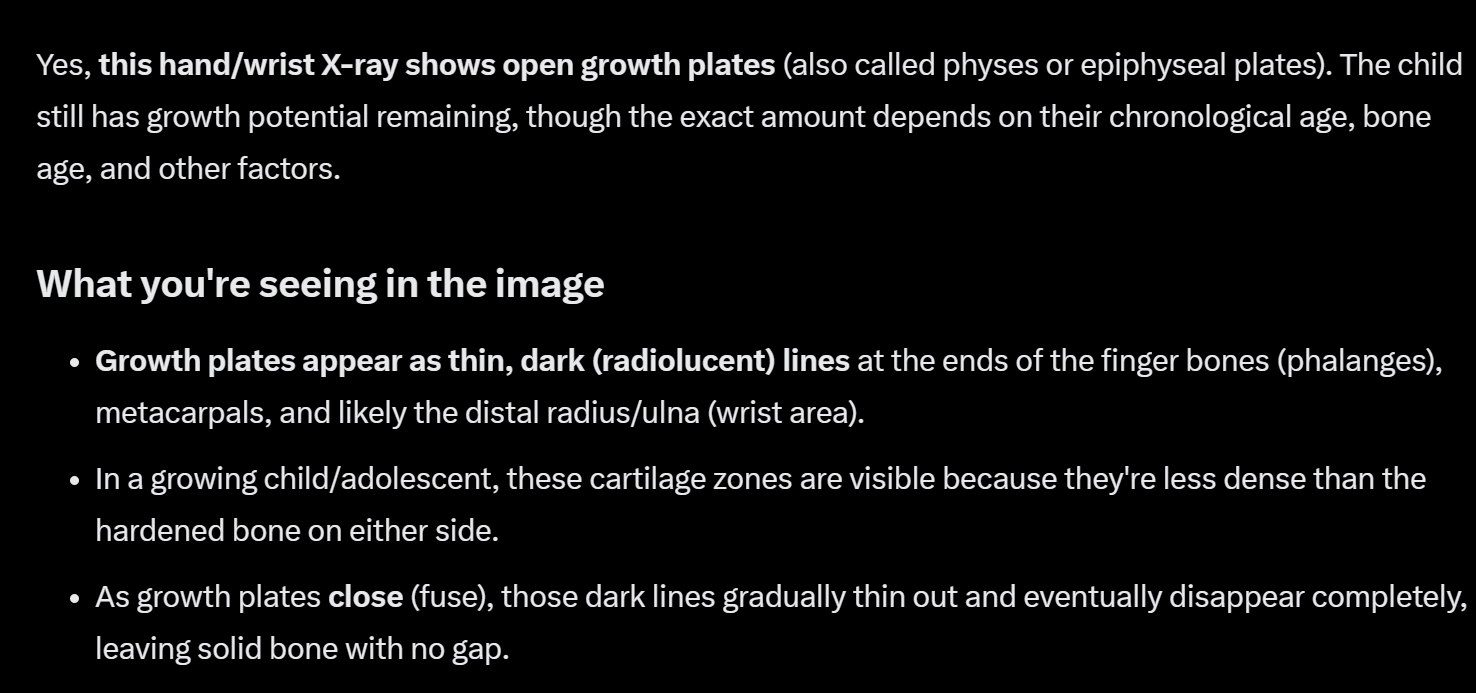

Bro I ask chat gpt he told me it’s over it’s full closed what a hell this Ai have you useHey there's this crazy thing called Artificial Intelligence that has literally been used to spot cancers on X-rays.

View attachment 4879748

@GrokBro I ask chat gpt he told me it’s over it’s full closed what a hell this Ai have you use